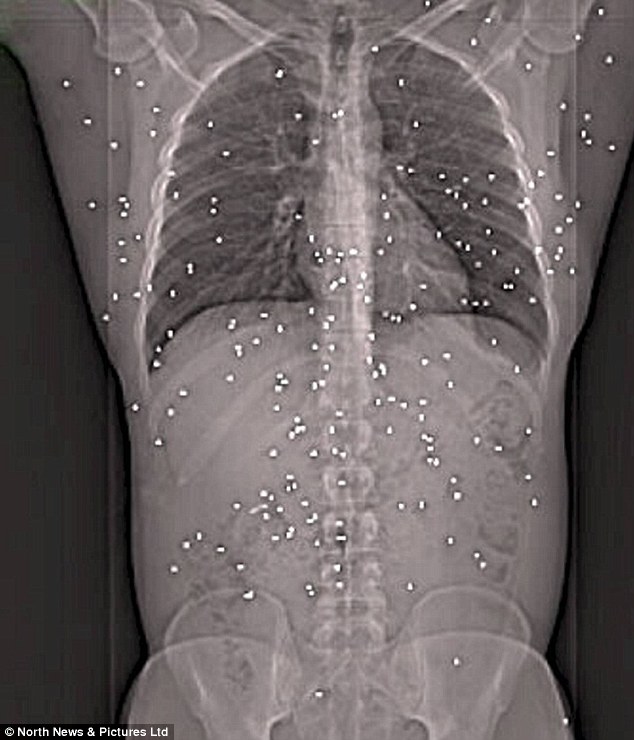

Jiran Tersalah Tembak, Budak Cedera Parah Terkena 13 Peluru Penabur Sesat

adik2 semua..peluru senapang patah macam ni  yer, dalam sebiji peluru tu ada bebola besi macam ni

tu sebab dinamakan peluru penabur

biler tembak nnt peluru pecah keluar bebola besi gini